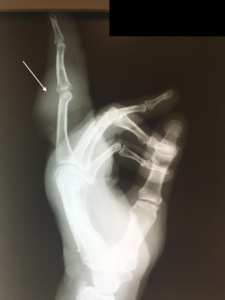

The patient underwent follow up with dermatology during the postoperative period. Suspicion for recurrence prompted biopsies that confirmed SCC recurrence. A third surgery was performed in March 2011. The surgery included removal of second and fifth digit, partial metacarpal resection. A PA pre-surgical radiograph was taken at the clinic and included in this report (Figure 3). Pathology identified metastatic squamous cell carcinoma with negative surgical margins, or no tumor pathologically identified at edges of biopsy.